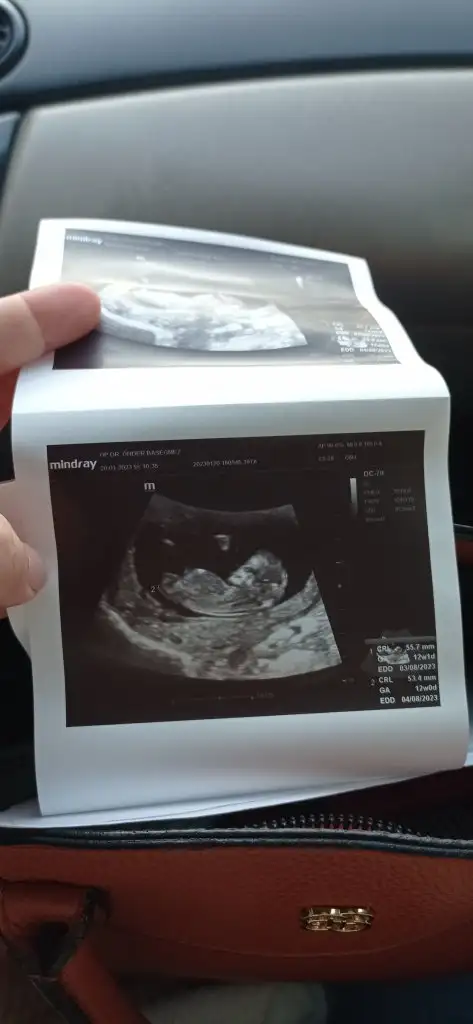

Nub,skull ve cinsiyet

bana da bakar mısınız ☺️

Sizinki nubunu kapatmis ben goremedim ama icime erkek dogdu nedense ilerleyen zamnda giderseniz tekrar foto atarmisiniz

Bende hamile olduğumu öğrenmeden önce rüyamda erkek olduğunu görmüştüm ve hep erkek olarak hissediyorum ama şu an 15 haftalık erkek olsaydı çoktan öğrenirdin diyorlar

Evt bende bu dusuncedeyim erkekler onceden belli ediyo nubunu goremedim malesef ☺️ tamamen his oda 100 de 50 50 zaten😚

• IMG_20230120_162530.webp

IMG_20230120_162530.webp

12 KB · Görüntüleme: 113